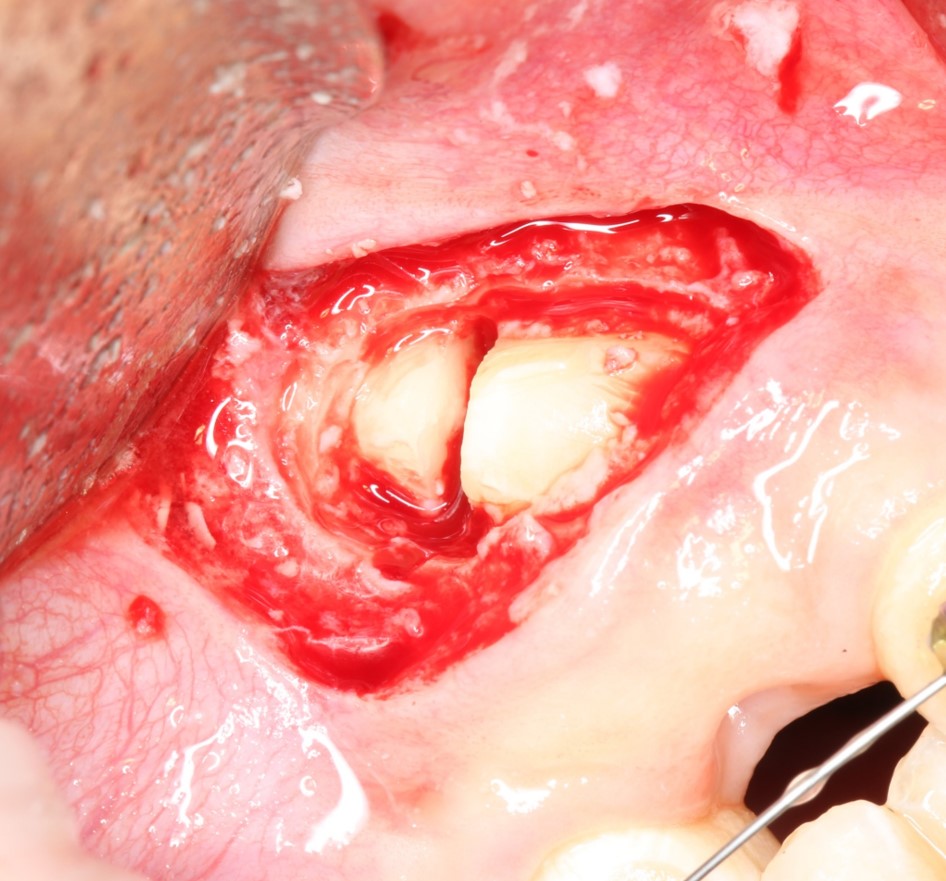

Иссечение воспаленной десны над зубом (того самого «капюшона), с последующей обработкой и дренажем образовавшейся раны.

Такая тактика оправдана в случае, если:

— по данным рентгенодиагностики (КЛКТ или ортопантомограммы) зуб находится в стадии прорезывания (верхушки корней не сформированы), ось прорезывания зуба имеет более-менее правильное направление, его коронковая часть не повреждена кариесом.

— врач-ортодонт подтверждает, что для прорезывания третьего моляра есть необходимое пространство (хватит места в зубном ряду), нет патологии прикуса и признаков развивающейся зубочелюстной аномалии.

— подобное состояние (перикоронит) у тебя впервые, и ты раньше никогда с ним не сталкивался.

— тебе не больше 20 лет.

При совпадении всех четырех условий, КОМПЕТЕНТНЫЙ хирург-стоматолог с помощью скальпеля иссечет десну над коронковой частью прорезывающегося зуба, остановит кровотечение, дренирует образовавшуюся рану, сделает послеоперационные назначения (как правило, они включают в себя антибактериальную и противовоспалительную терапию, а также уход за областью послеоперационной раны) и запишет тебя на послеоперационные осмотры, которые ни в коем случае нельзя игнорировать.